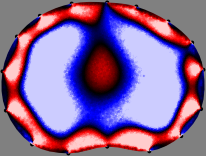

Figs. 3 and 4 compare the performance of the proposed FER method in (20) with the standard regularized least-squares method ((19) when \mathcal{R} is the identity matrix). The regularization parameter of the standard method was heuristically chosen for its best performance, and the parameter of the FER method was set to be one of three different values λ=0.05,0.2,𝜆0.050.2\lambda=0.05,0.2,\infty. The injection current was 1 mARMSRMS{}_{\tiny{\mbox{RMS}}} at 100 kHz, and the frame rate was 9 frames per second. The reference frame at t0subscript𝑡0t_{0} was obtained from the maximum expiration state. The measured data, 𝐕˙(tm)˙𝐕subscript𝑡𝑚\dot{\mathbf{V}}(t_{m}), represent the voltage differences between each time tmsubscript𝑡𝑚t_{m} and t0subscript𝑡0t_{0}. The blue regions, which denote where conductivity decreased by inhaled air, increased during inspiration and decreased during expiration. The FER method with λ=𝜆\lambda=\infty was clearly more robust than the standard method that produced more artifacts originated from the inversion process.

Figure 4: The reconstructed images of the conductivity change of the subject B by the standard regularized least square method and the proposed fidelity-embedded regularization (FER) method for three difference values λ=0.05,0.2,𝜆0.050.2\lambda=0.05,0.2,\infty. Here, the time step is 0.55 seconds (tm+5tm0.55subscript𝑡𝑚5subscript𝑡𝑚0.55t_{m+5}-t_{m}\approx 0.55).